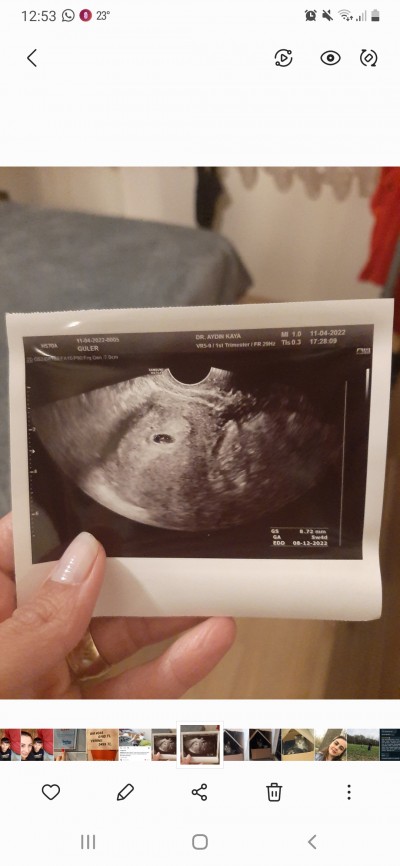

Ilk ultrason goruntudu

Ilk ultrason goruntusu

Gebelik haftası

10+6

Haftana gore cok kucuk degilmi anlayamadim

5 haftalikken bakilmis galiba kağıtta öyle yaziyo

5 haftalık sasirdigim icin soruyorum bende 10num en son goruntu kocaman

Haftana göre bana küçük geldi ben 8 haftalıkken gitmiştim seninkinden biraz daha büyük

5 haftalık ultrasyon kağıdı zaten kızlar

Eski tarihli ultrason görüntüsü nisanda çekilmişte. Ne sormak istemiş onu anlamadım

Ben 11 haftalıkken yapmıştım onda bübek tam görünüyordu ayakları kafası bedeni.

Bende 6 haftalıkken böyleydi

Nisanda çekilmiş ozaman kaç haftalıktı şimdi kaç jaftalık bu ay daha net göre bilirsin